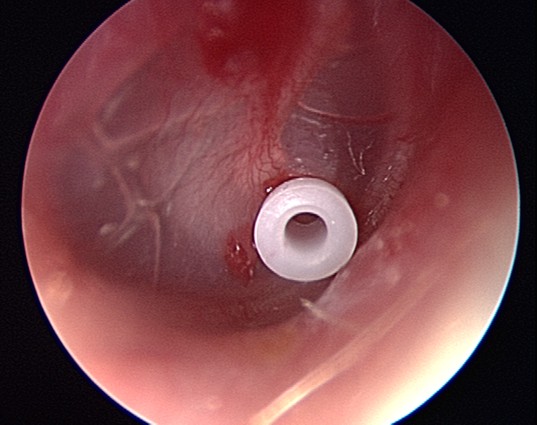

Si l'infection de l'oreille revient sans cesse ou dure longtemps, votre médecin peut suggérer une intervention chirurgicale.

Les traitements chirurgicaux consistent notamment en l'introduction d'un tube de ventilation dans le tympan pour drainer les fluides ou en l'ablation des adénoïdes gonflées ou enflammées (adénoïdectomie), où les bactéries peuvent se multiplier et empêcher le drainage naturel dans la gorge.

À propos des tubes de ventilation et de l'adénoïdectomie.

Pour aider à maintenir l'oreille moyenne de votre enfant exempte d'accumulation de fluide et d'infection, un médecin doit insérer des tubes de ventilation dans les oreilles ou pratiquer l'ablation des adénoïdes (adénoïdectomie électrochirurgicale).

Les tubes de ventilation d'oreille ou une adénoïdectomie électrochirurgicale aident à empêcher l'accumulation de fluide dans l'oreille et son infection. La méthode utilisée dépend de l'état de votre enfant et de ce qui cause les infections de l'oreille.

De quoi s'agit-il ?

Votre pédiatre peut recommander des tubes de ventilation pour votre enfant si celui-ci a une infection de l'oreille et qu'il

reste du fluide dans l'oreille après le traitement initial ou si votre enfant a eu plusieurs infections de l'oreille dans l'année.

Que sont les tubes de ventilation d'oreille ?

Les tubes de ventilation d'oreille ont généralement une largeur de quelques millimètres.

Le fluide emprisonné derrière le tympan est un terrain propice aux bactéries et à l'infection. Un tube de ventilation d'oreille est un très petit tube qui est placé dans le tympan. Il est aussi appelé aérateur transtympanique, tube de tympanostomie,tube d'égalisation de pression, yo-yo ou encore diabolo. Les tubes de ventilation permettent l'écoulement du fluide emprisonné derrière le tympan, ce qui aide à prévenir les infections de l'oreille (otite moyenne).

L'insertion d'un tube de ventilation est une opération simple. Les ORL pratiquent une très petite incision dans le tympan et insère un tube de ventilation dans l'oreille ou dans les deux oreilles. Les tubes de ventilation ne causent ni douleur, ni perte d'audition.

Chez les enfants, l'insertion d'un tube de ventilation s'effectue généralement sous anesthésie générale à l'hôpital.

À quoi servent les tubes de ventilation ?

Il arrive que les trompes d'Eustache d'un enfant n'arrivent pas à drainer le fluide de l'oreille

moyenne dans la gorge. Si le fluide s'accumule derrière le tympan, les bactéries peuvent se développer. C'est ainsi que les infections de l'oreille commencent. Après la disparition d'une infection de l'oreille, il reste souvent du fluide derrière le tympan.

Un très petit tube de ventilation de l'oreille est introduit dans le tympan pour permettre le drainage du fluide et empêcher parfois le retour d'infections.